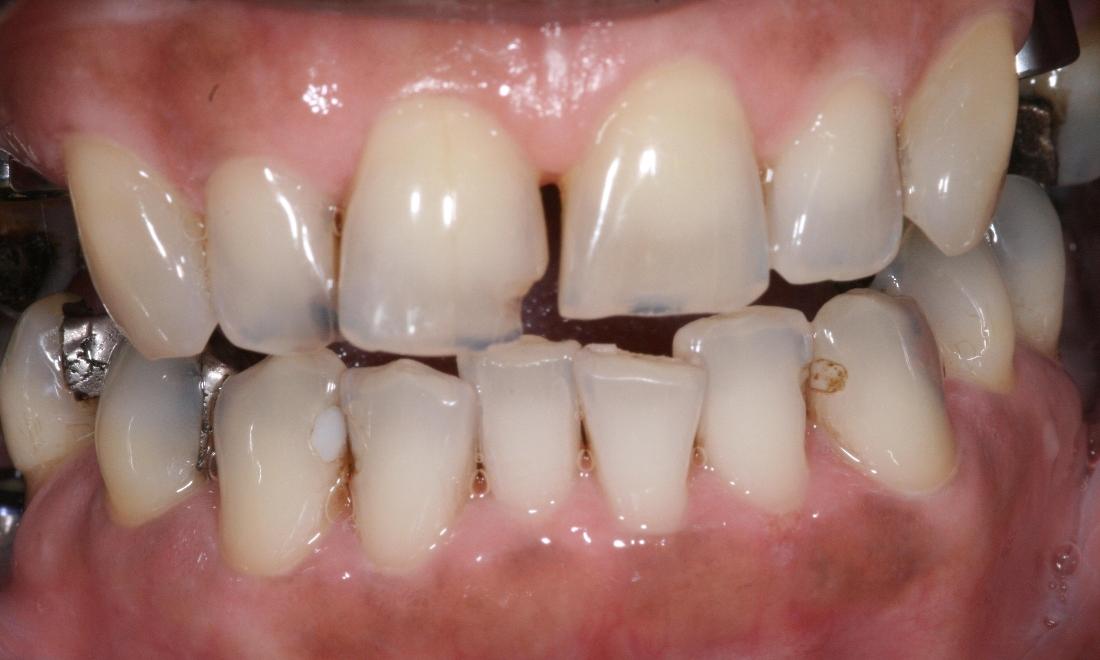

Above all, we are committed to offering and delivering exceptional, comprehensive dental care to each and every one of our clients. Through a unique mix of ultra-contemporary office design elements; the finest dental technologies, materials, and treatments; and a strong emphasis on exemplary customer service, it is our mission to create a practice environment which fosters the highest level of patient comfort safety, and overall satisfaction. We strive to protect the health of our patients and add beauty to their smiles. We will not be satisfied until we have perfected THE ultimate experience - one that includes Five Star service, extraordinary dentistry and makes a positive, lasting impression on the lives of our patients.